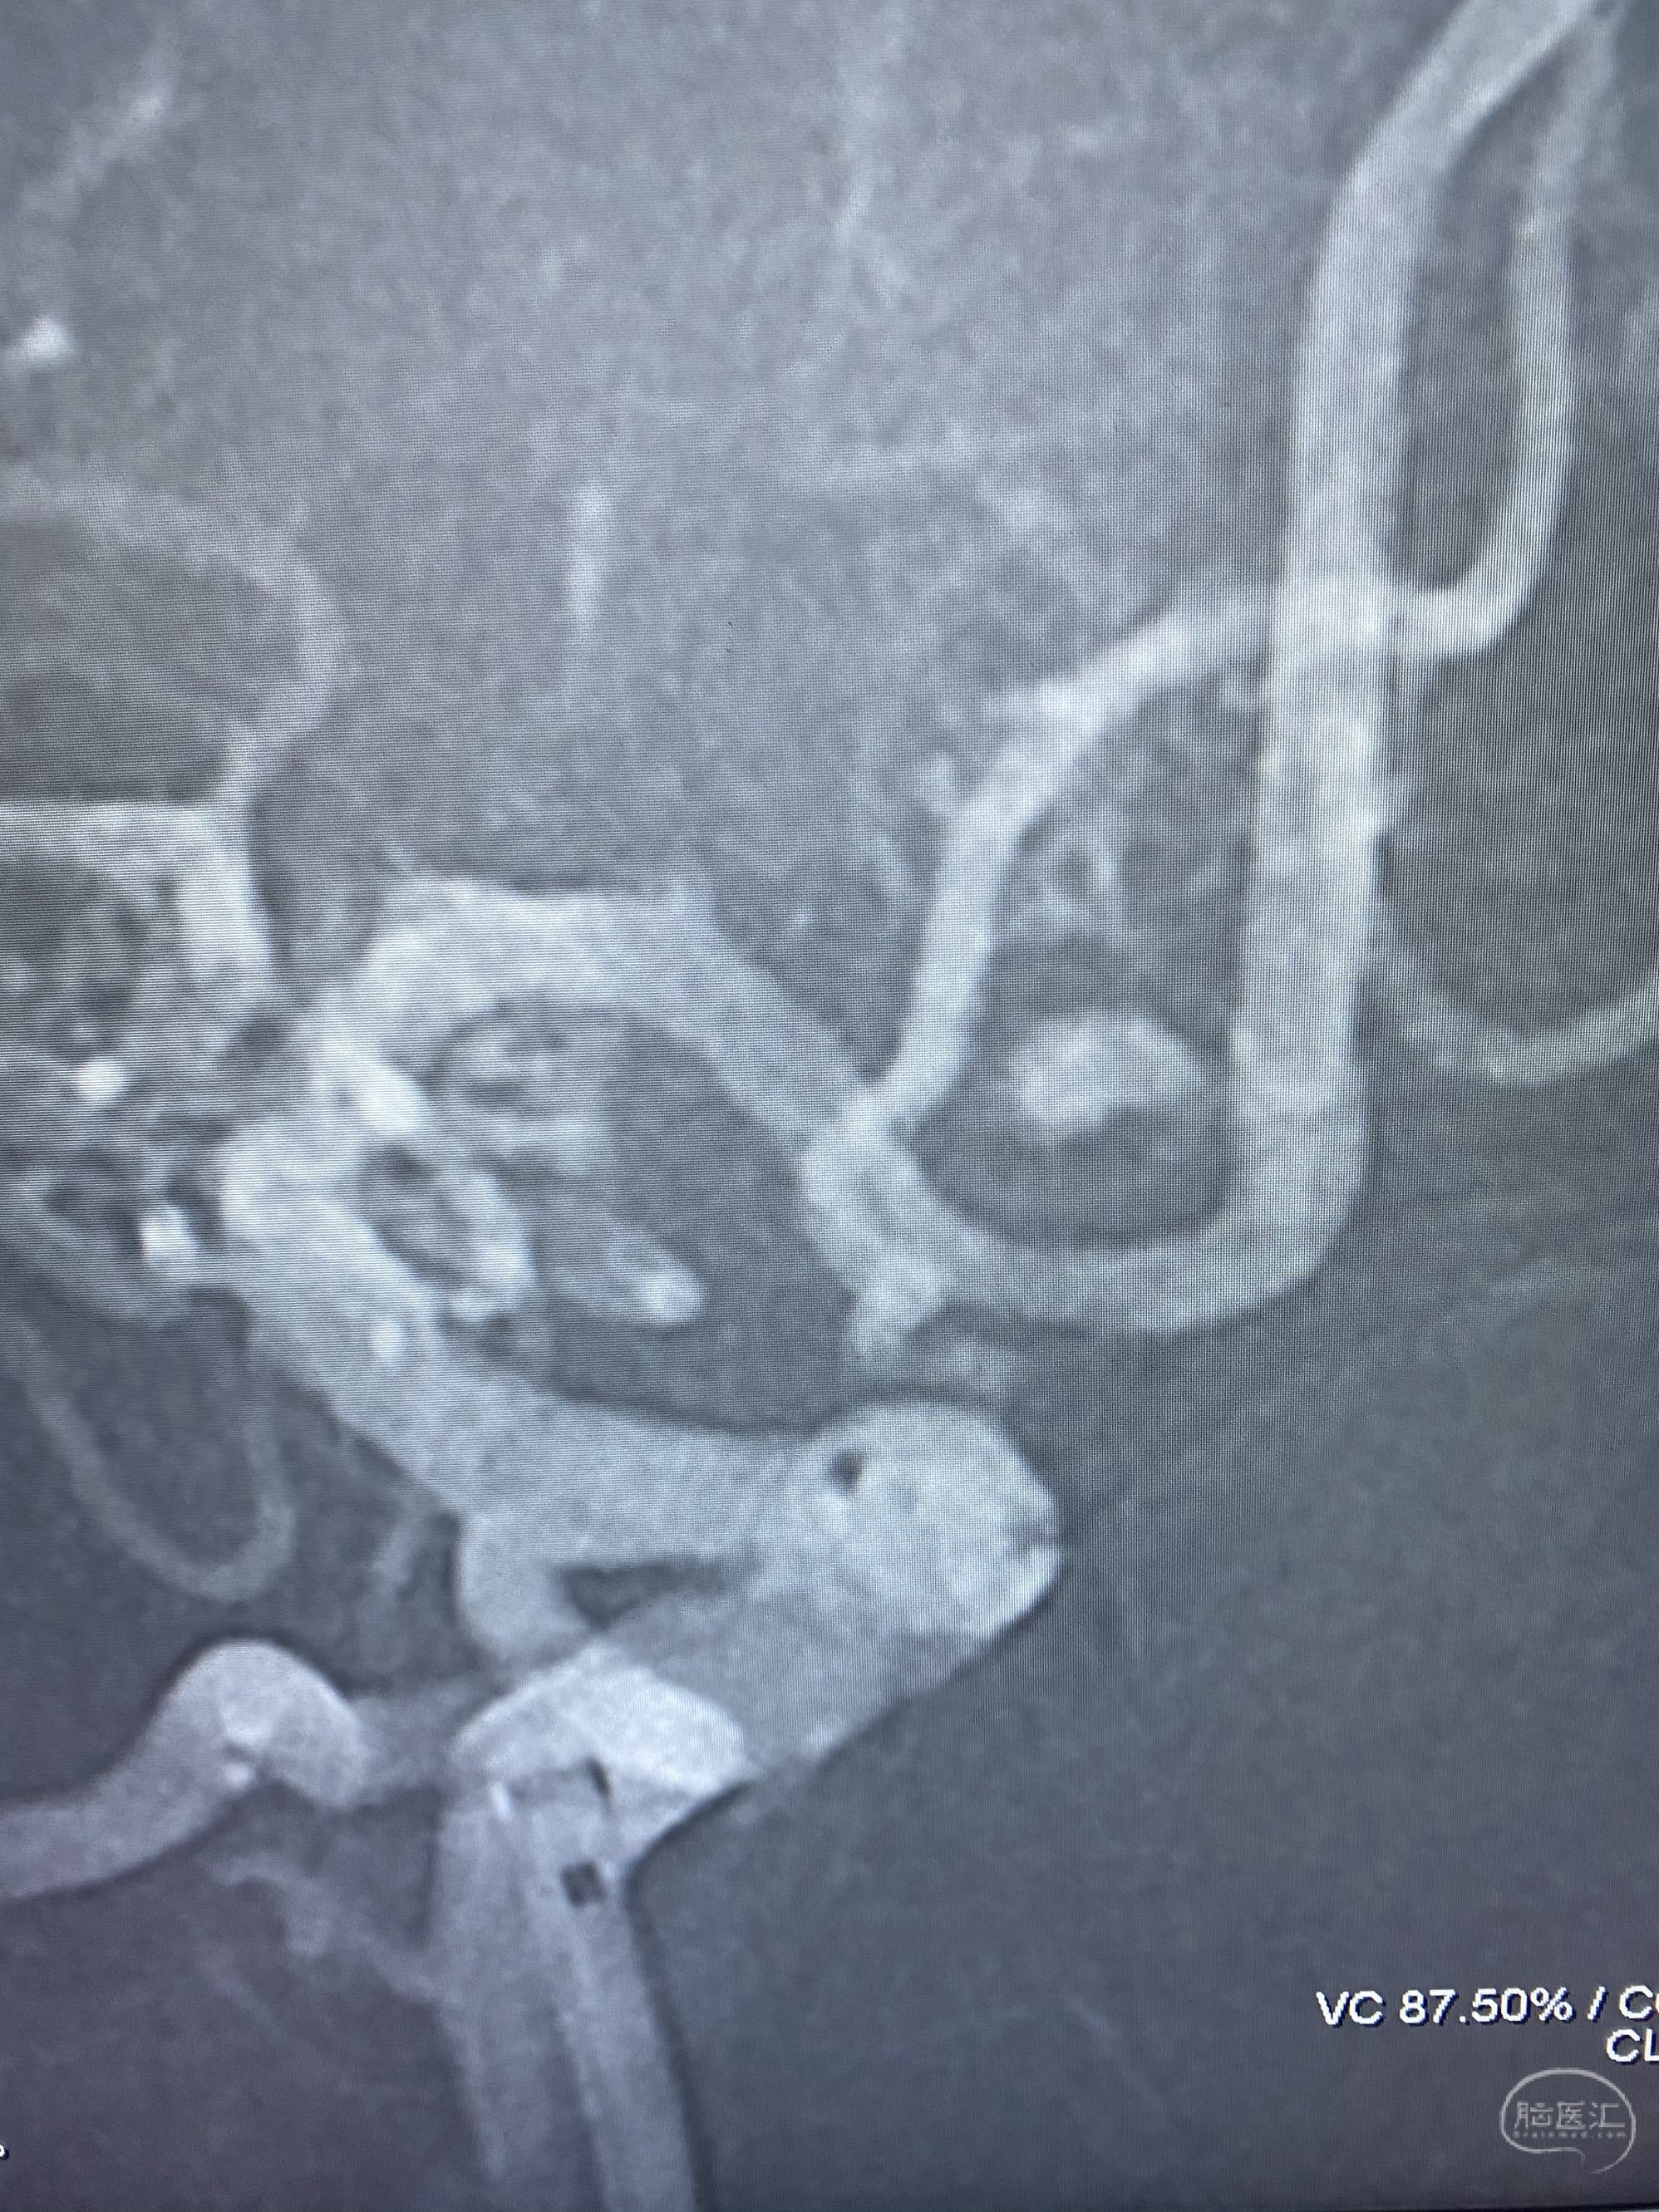

MLS,M79Y,sah,双侧MCA烟雾病,Heubner返动脉瘤,前交通段开窗,细支发出Heubner返动脉,瘤颈细长,瘤颈口比微导管细,弹簧圈2mmx3cm“隔山打牛”填塞治愈,Heubner返动脉保留。

该患者术后2天观察神志清楚,四肢活动正常。

Heubner返动脉是由大脑前动脉A1末端发出的豆纹动脉,由于走形和A1段相反,故称Heubner返动脉,该动脉梗塞可能引起尾状核头梗塞,引起偏瘫和面瘫,便身震颤等症状。